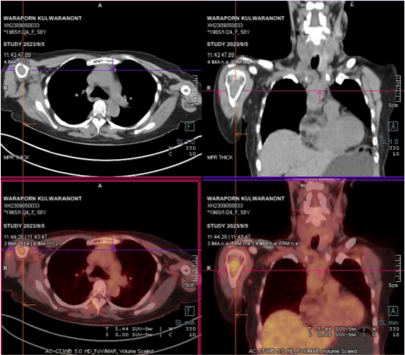

Professor Li said in an interview: "Ms. M's disease has reached an advanced stage, with some adverse biological features after healing, including abnormalities in 1q21 and the presence of extramedullary masses found by PET-CT. Therefore, conventional treatments would definitely be ineffective."

On September 8, 2023, Ms. M finally received the last lifeline and officially entered the CAR-T treatment process. After all examination items met the requirements, single-cell collection was performed first.

Hope was within reach, but Ms. M's physical condition deteriorated, and cancer cells crazily consumed her weakening body. The left pleural cavity was also infiltrated by cancer cells. At this point, doctors were using various methods to slow down the spread of cancer, while a customized production line was tailoring precise killing weapons for Ms. M. Everyone was racing against time to gain more time from death.

Bridge therapy began on September 11, 2023;

Local radiotherapy to relieve bone pain started on September 24, 2023;

Fludarabine plus cyclophosphamide chemotherapy was administered from October 9-12, 2023;

Finally, on October 14, 2023, the CAR-T cells carrying the hopes of Ms. M's family were delivered to her by the pharmacy team using professional cold chain logistics. After layers of testing, unpacking, and reconstitution, a small bag of milky-white liquid was infused into Ms. M's body. The doctor said that inside were billions of "special" T cells that could precisely kill multiple myeloma cells. Once inside the body, they would initiate a mode of frenzied sweeping, wiping out cancer cells completely.